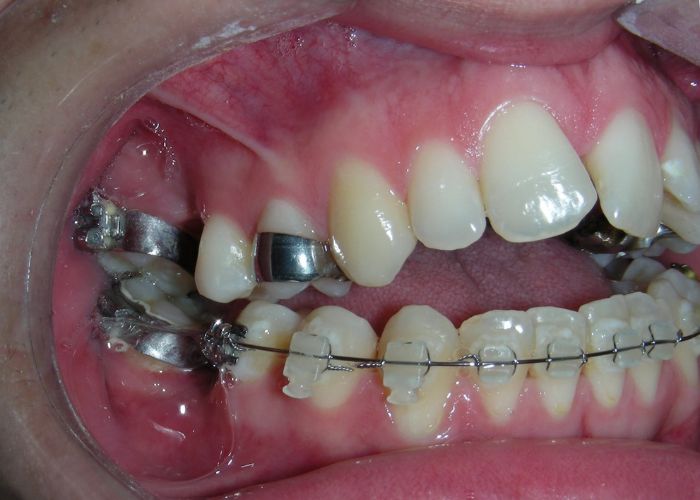

Having successfully achieved the expansion, we proceed to the intrusion of the posterior superior sectors, modifying the Hyrax by adding anchoring hooks at the buccal level of the first premolars. Using the Hyrax as anchorage, we sought a parallel intrusion. This could be replaced by a palatal bar. TADs were installed bilaterally at the mesial level of the first molars, inserting them as parallel as possible to the roots.

Clinical changes became evident after 12 months of treatment with posterior intrusion with TADs and nickel-titanium closed coil spring (NiTi), until subsequent follow-up appointments revealed no further significant changes. At that point, it was noted that the most distal molars remained in occlusal contact and had not followed the intrusive movement of their mesial neighbors.

The vertical vector of intrusion was located too far posteriorly to allow for the placement of TADs in that region. At this point, the utility arch developed by Dr. Ricketts was introduced into the mechanics . I referred to as the “Tilting Utility Arch.” made with Blue Elgiloy .017″ × .025″. It was employed as a lever arm to transmit the intrusive force generated by the coil spring and anchored by the TADs.

The upper brackets were bonded solely for the purpose of providing stability to the utility arch . Following the hierarchically structured treatment plan, we proceed with the alignment and leveling phase in order to enable mesialization of the posterior segments using sliding mechanics, which works effectively in conjunction with Roth prescription brackets .022.